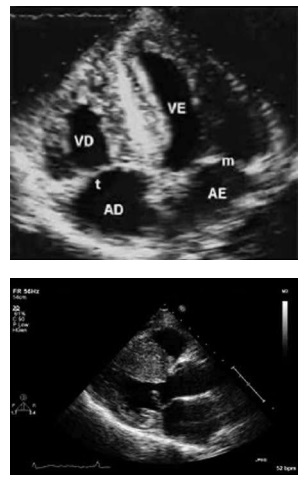

Com base na situação hipotética apresentada e nas

imagens resultantes da realização do POCUS, assinale a

alternativa correta.Provas

Um homem de 45 anos de idade, tabagista com

30 anos/maço e hipertenso, foi ao pronto-socorro e

relatou desconforto precordial de início há algumas horas,

inespecífico. Não soube informar fatores de melhora ou

de piora, sem irradiações. Foi realizado eletrocardiograma,

mostrado a seguir.